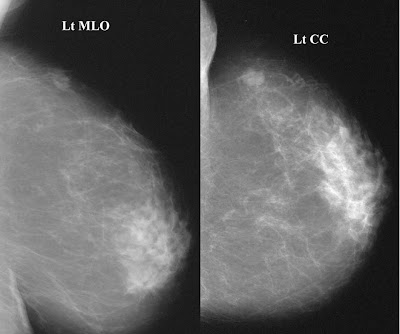

A composição mamária está relacionada às quantidades relativas de tecido adiposo e fibroglandular e dá origem aos chamados padrões mamográficos, que estão divididos em:

- Mamas predominantemente adiposas (25% do componente fibroglandular).

- Mamas parcialmente gordurosas (com densidades de tecido fibroglandular ocupando de 26% a 50% do volume da mama).

- Mamas com padrão denso e heterogêneo (51% a 75% de tecido fibroglandular, dificultando a visibilização de nódulos).

- Mamas muito densas, apresentando mais de 75% de tecido fibroglandular (diminuindo a sensibilidade da mamografia).